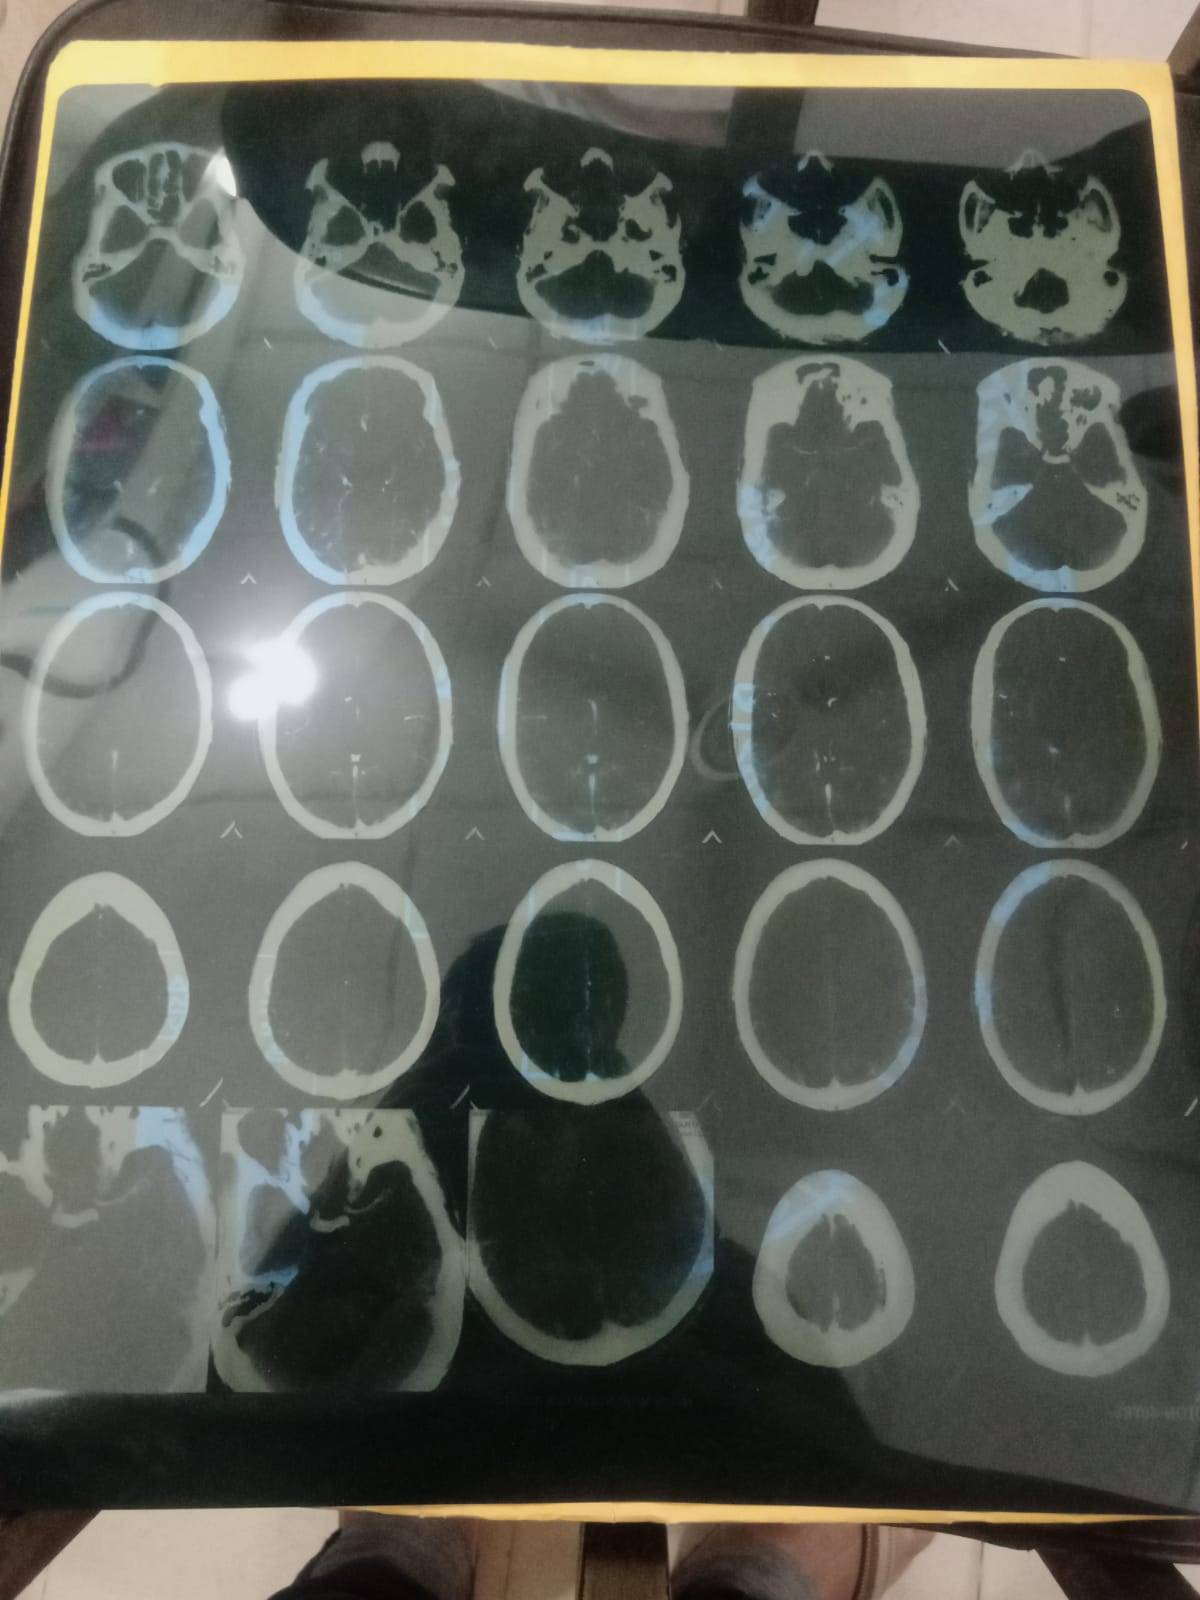

আজ আমি একজন অসহায় মানুষের পক্ষ থেকে আপনাদের কাছে আবেদন জানাতে লিখছি। চন্দন কুমার দাস (ডাকনাম রতন) একজন সাধারণ নাপিত। তিনি দিন এনে দিন খাওয়া মানুষ। হঠাৎ করে ব্রেইন স্ট্রোকে আক্রান্ত হয়ে বর্তমানে তিনি কর্মক্ষমতা হারিয়েছেন। যে মানুষটি প্রতিদিন পরিশ্রম করে সংসার চালাতেন, আজ তিনি নিজেই অন্যের সহায়তার মুখাপেক্ষী।

তার পরিবারে একজন শারীরিক প্রতিবন্ধী সন্তান রয়েছে। স্ত্রী একাই সবকিছু সামলানোর চেষ্টা করছেন, কিন্তু আর্থিক সংকট এখন সবচেয়ে বড় বাধা হয়ে দাঁড়িয়েছে। চিকিৎসকের পরামর্শ অনুযায়ী নিয়মিত ওষুধ এবং ফিজিওথেরাপি চালিয়ে যেতে পারলে ধীরে ধীরে উন্নতি সম্ভব। কিন্তু প্রয়োজনীয় চিকিৎসা ব্যয় বহন করা এই পরিবারের পক্ষে অত্যন্ত কঠিন হয়ে পড়েছে।